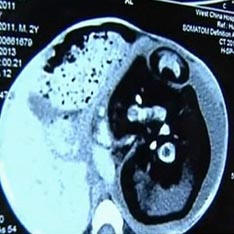

I chirurghi hanno trovato il nascituro nello stomaco di un bambino di due anni Gemello siamese. Con un caso insolito nella sua pratica affrontato medici dalla Cina. Dopo che i medici hanno esaminato un bambino di due anni con una pancia enorme del villaggio di Huashi, si è scoperto che in lui c’era il suo gemello non ancora nato. Fu deciso di sottoporsi a un’operazione di emergenza, poiché lo stomaco era gonfio dimensioni incredibili, gli organi interni hanno cominciato a spremere e è diventato difficile per il bambino respirare, scrive il Daily Mail. Si è scoperto che quel fratello, che era dentro di lui per tutto questo tempo, non era molto più piccolo del ragazzo stesso. Il suo corpo era sottosviluppato, ma la colonna vertebrale, gli arti e le dita su braccia e gambe sono completamente formati. Questo il caso, hanno spiegato i medici, è una delle varietà di siamese i gemelli. Nascono quando un uovo fecondato non completamente condiviso. Ma, come ha notato il neonatologo della scuola materna Cleatand Hospital Dr. Jonathan Fanarof, nel caso di bambino “incinta”, l’uovo non ha condiviso.

Nell’intera storia della medicina, ci sono centinaia di casi in cui uno di embrioni gemelli viene “assorbito” da suo fratello e continua sviluppo al suo interno. Questo fenomeno si verifica sempre all’inizio. fasi della gravidanza, e di solito entrambi i feti muoiono nell’utero madre. Accade, tuttavia, che il parto abbia successo e sia coinvolto l’embrione della trappola continua a vivere come un parassita collegato al suo fratello maggiore una specie di cordone ombelicale. Alla fine lui diventa così grande che inizia a farsi del male al proprietario. In medicina, questa anomalia è chiamata feto nel feto (embrione nell’embrione). A proposito, lo stesso caso è stato registrato qualche anno fa in India. La pancia del 36enne Sanju Bhagat era gonfio così tanto che sembrava una donna che stava per farlo partorirà. I chirurghi erano sicuri di avere un tumore enorme, che preme sul diaframma. Ma quale fu la loro sorpresa quando uscì dalla sua tirarono fuori l’utero del corpo mutato di suo fratello gemello.